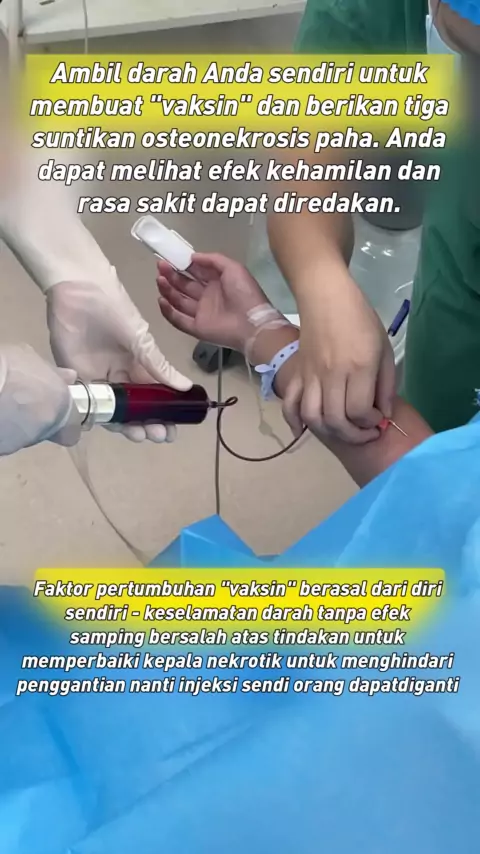

Terapi plasma trombosit kaya untuk nekrosis tulang femoralis # nekrosis femoralis # kesehatan # ilmu kedokteran